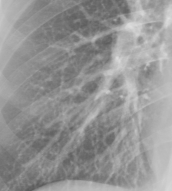

Refer to caption

(a)

(b)

(c)

(d)

Figure 8: Enhancement result on NIH ChestX-Ray14 image. One network was trained on the original X-ray and a second network was trained on the enhanced X-ray (a) Original X-ray (b) Enhanced X-ray (c) Zoom (d) Zoom -Enhanced